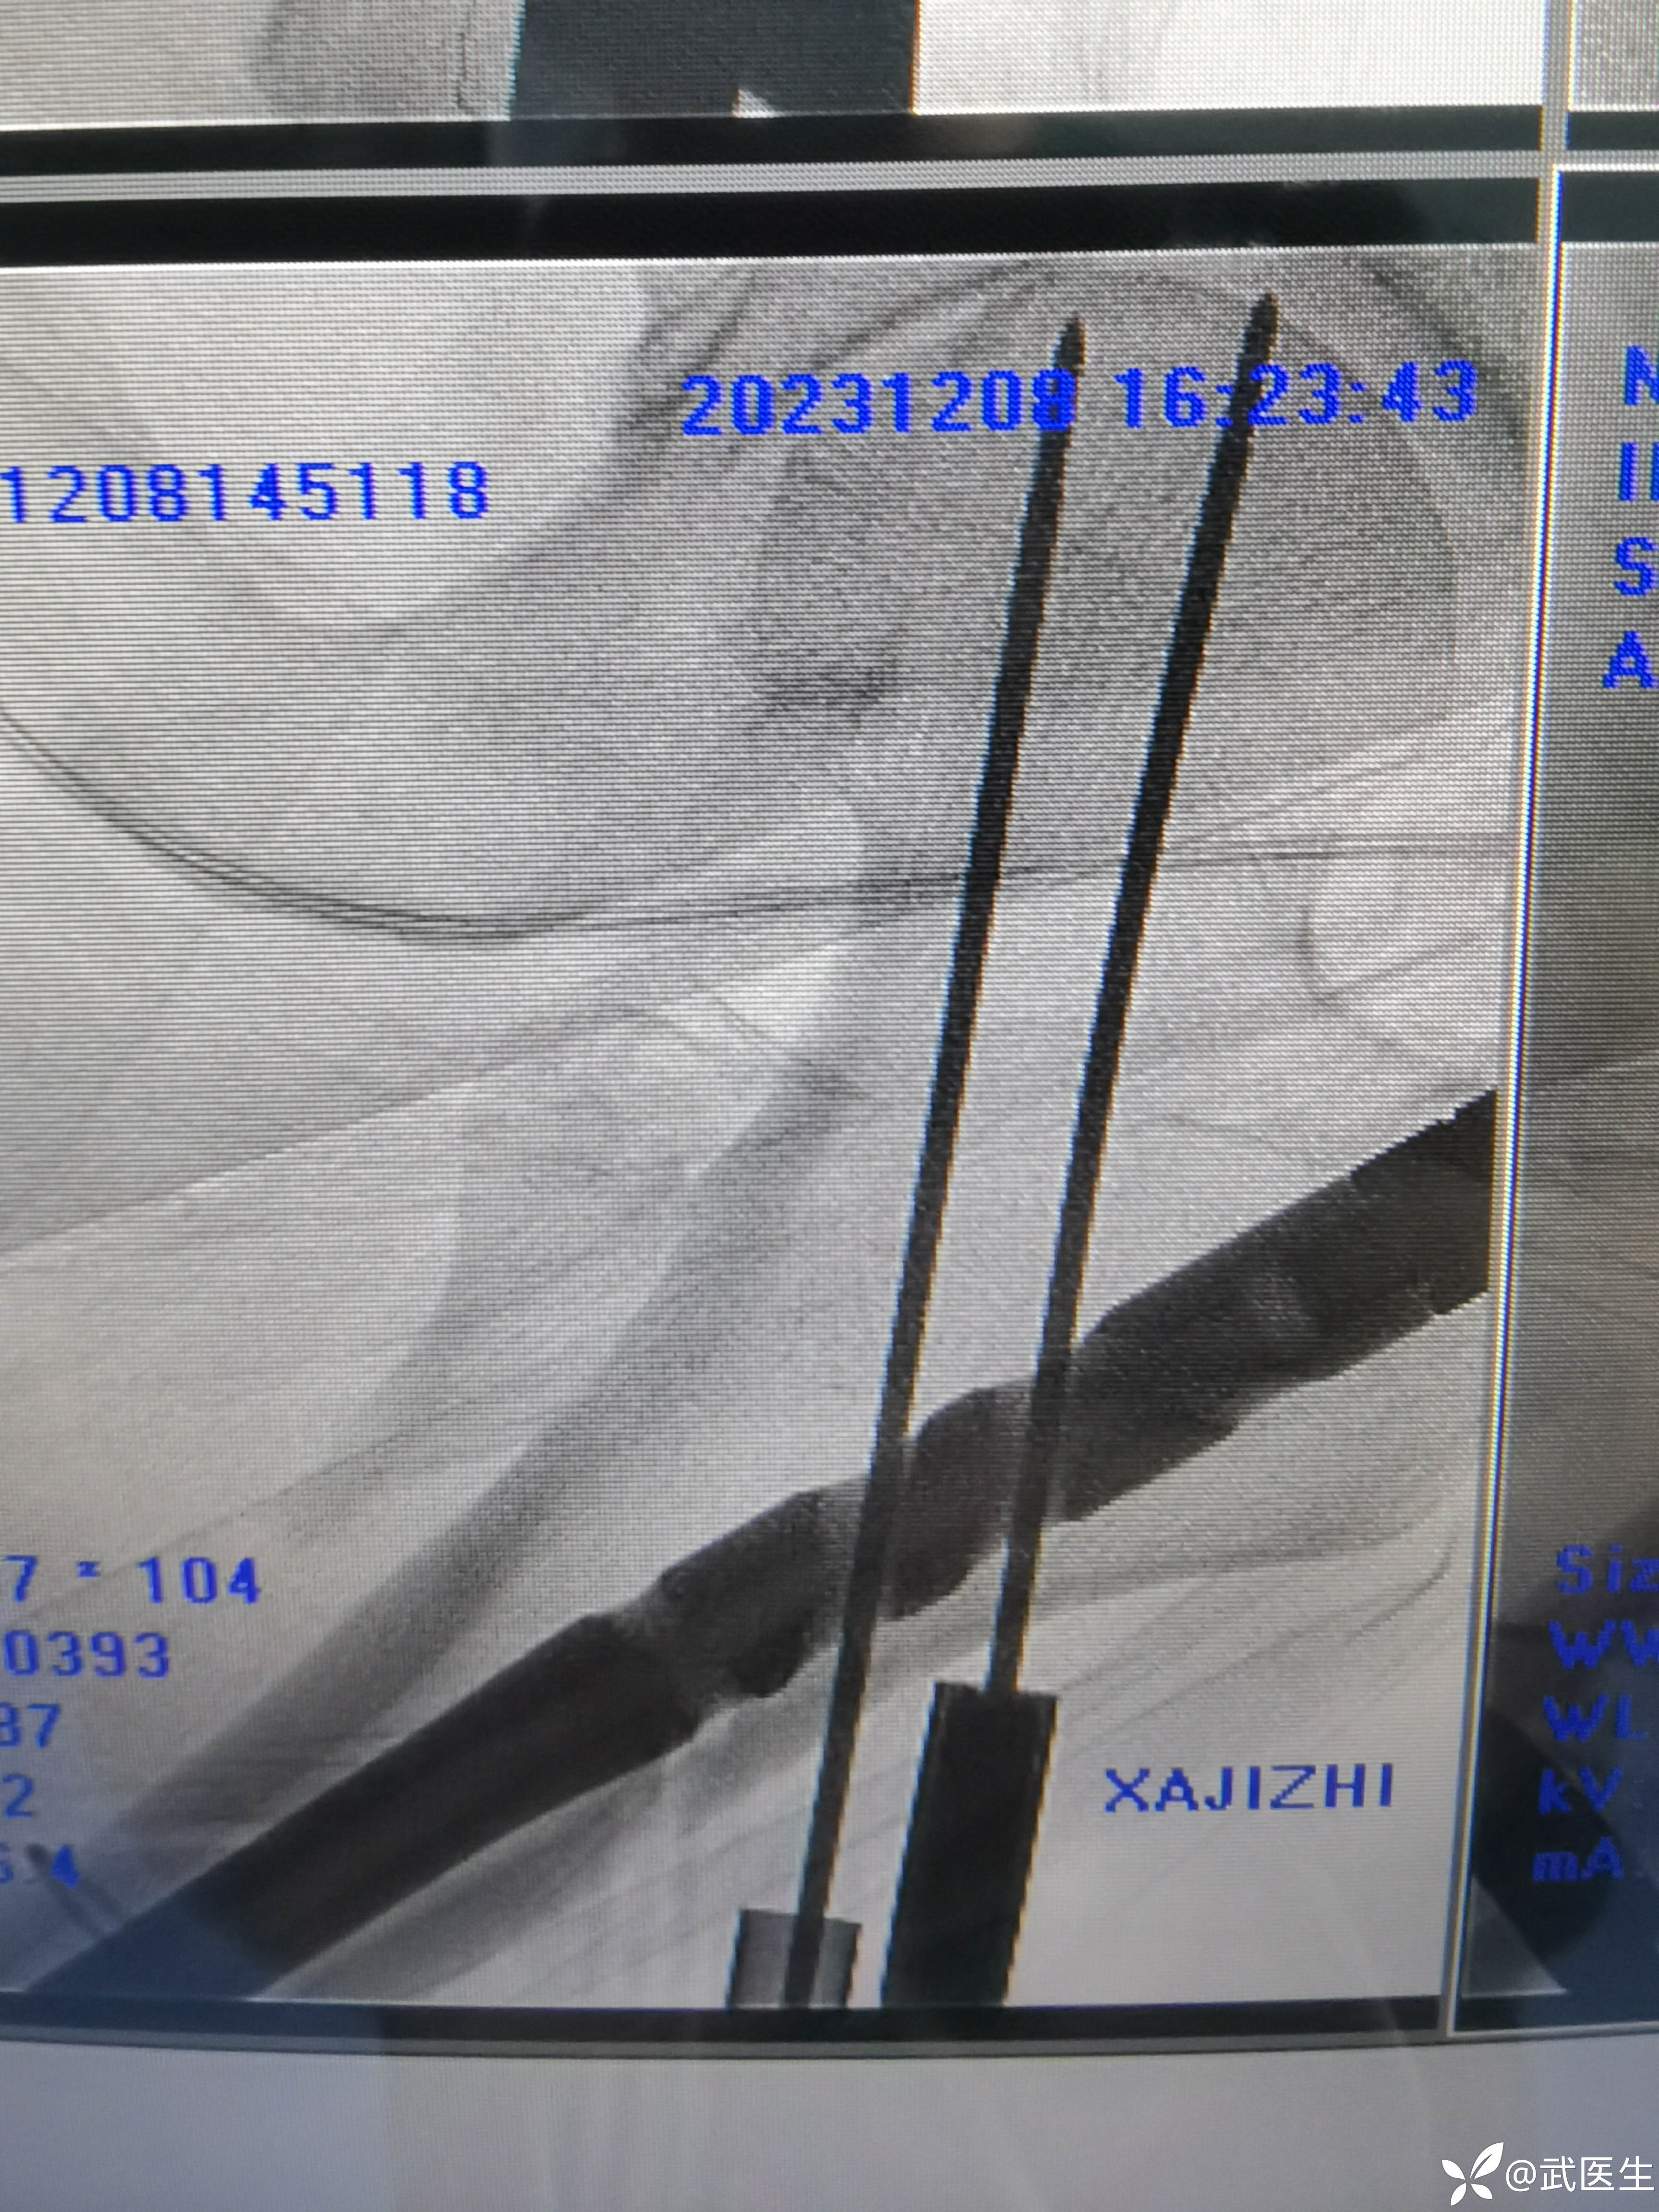

开口扩髓置钉,头颈导针,正位还行

轴位头颈导针还行